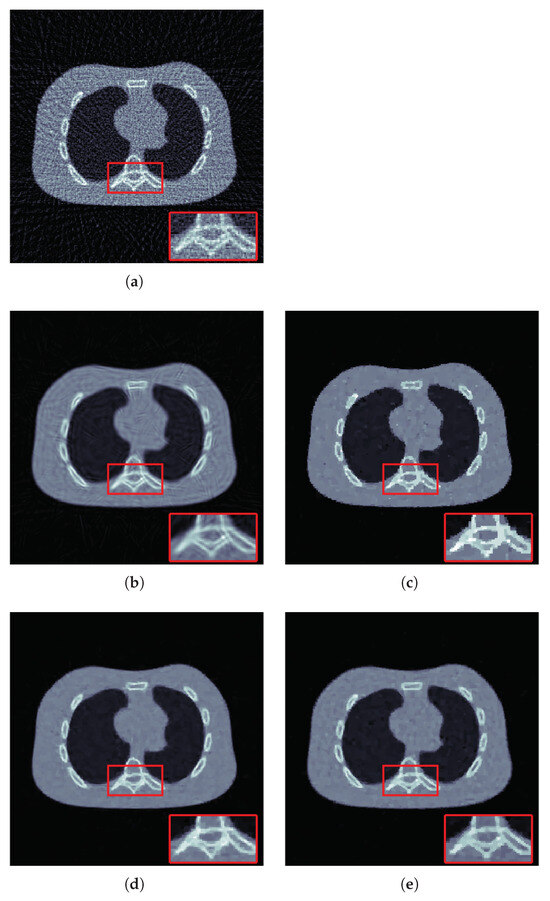

4.2. Results for Limited View Data

| # Photons | Method | PSNR | SSIM |

|---|---|---|---|

| FBP | 18.0747 | 0.3567 | |

| 22.8527 | 0.8449 | ||

| TV | 24.9294 | 0.9516 | |

| -TV | 24.6716 | 0.9289 | |

| proposed | 25.1727 | 0.9540 |